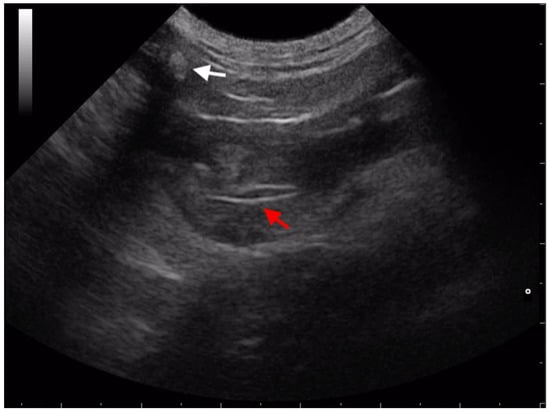

3.2. Retroperitoneal Migration